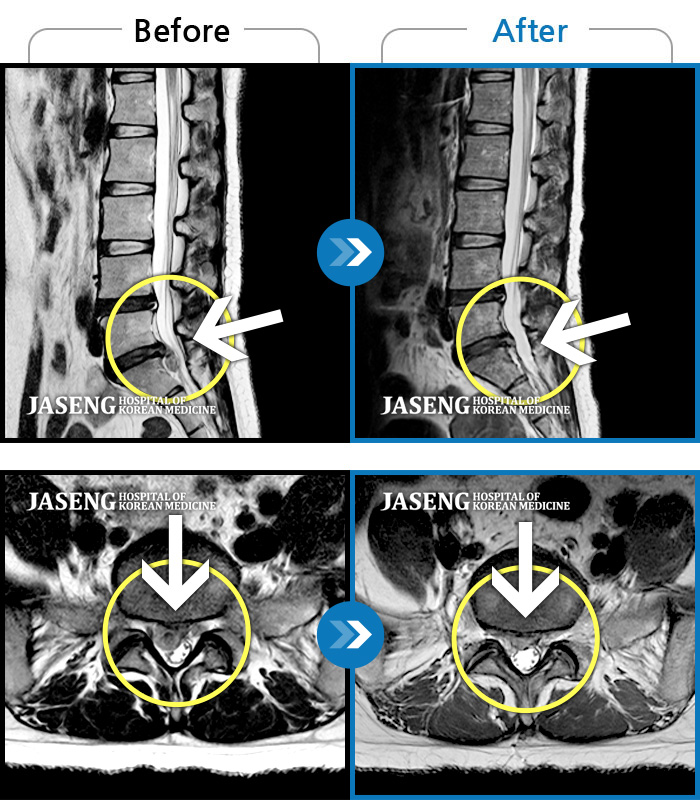

목과 왼쪽 팔에서 1,2번째 손가락까지 저리고 당기는 통증

2012.05.07 ~ 2013.03.13